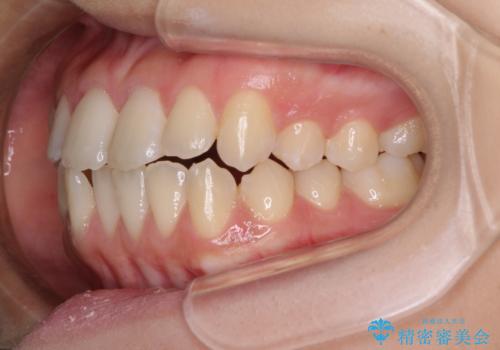

- 上下のデコボコと奥歯の咬みにくさを気にして来院された患者様です。

上顎骨の幅が下顎骨よりも小さく受け口傾向であったため、拡大装置により上顎骨の骨幅を広げて上下関係を改善し、その後インビザラインにて歯並びを整えることとしました。

下顎歯列は上顎歯列内に収まるように並んでいますが、上顎骨の幅が狭いと、下顎臼歯が全体的に舌側に傾斜した歯列となってしまいます。

舌側に傾斜した歯列は奥歯に力の負担がかかりやすく、歯磨きがしにくいなどの問題があるため、上顎骨拡大により舌側傾斜を改善することが可能となります。